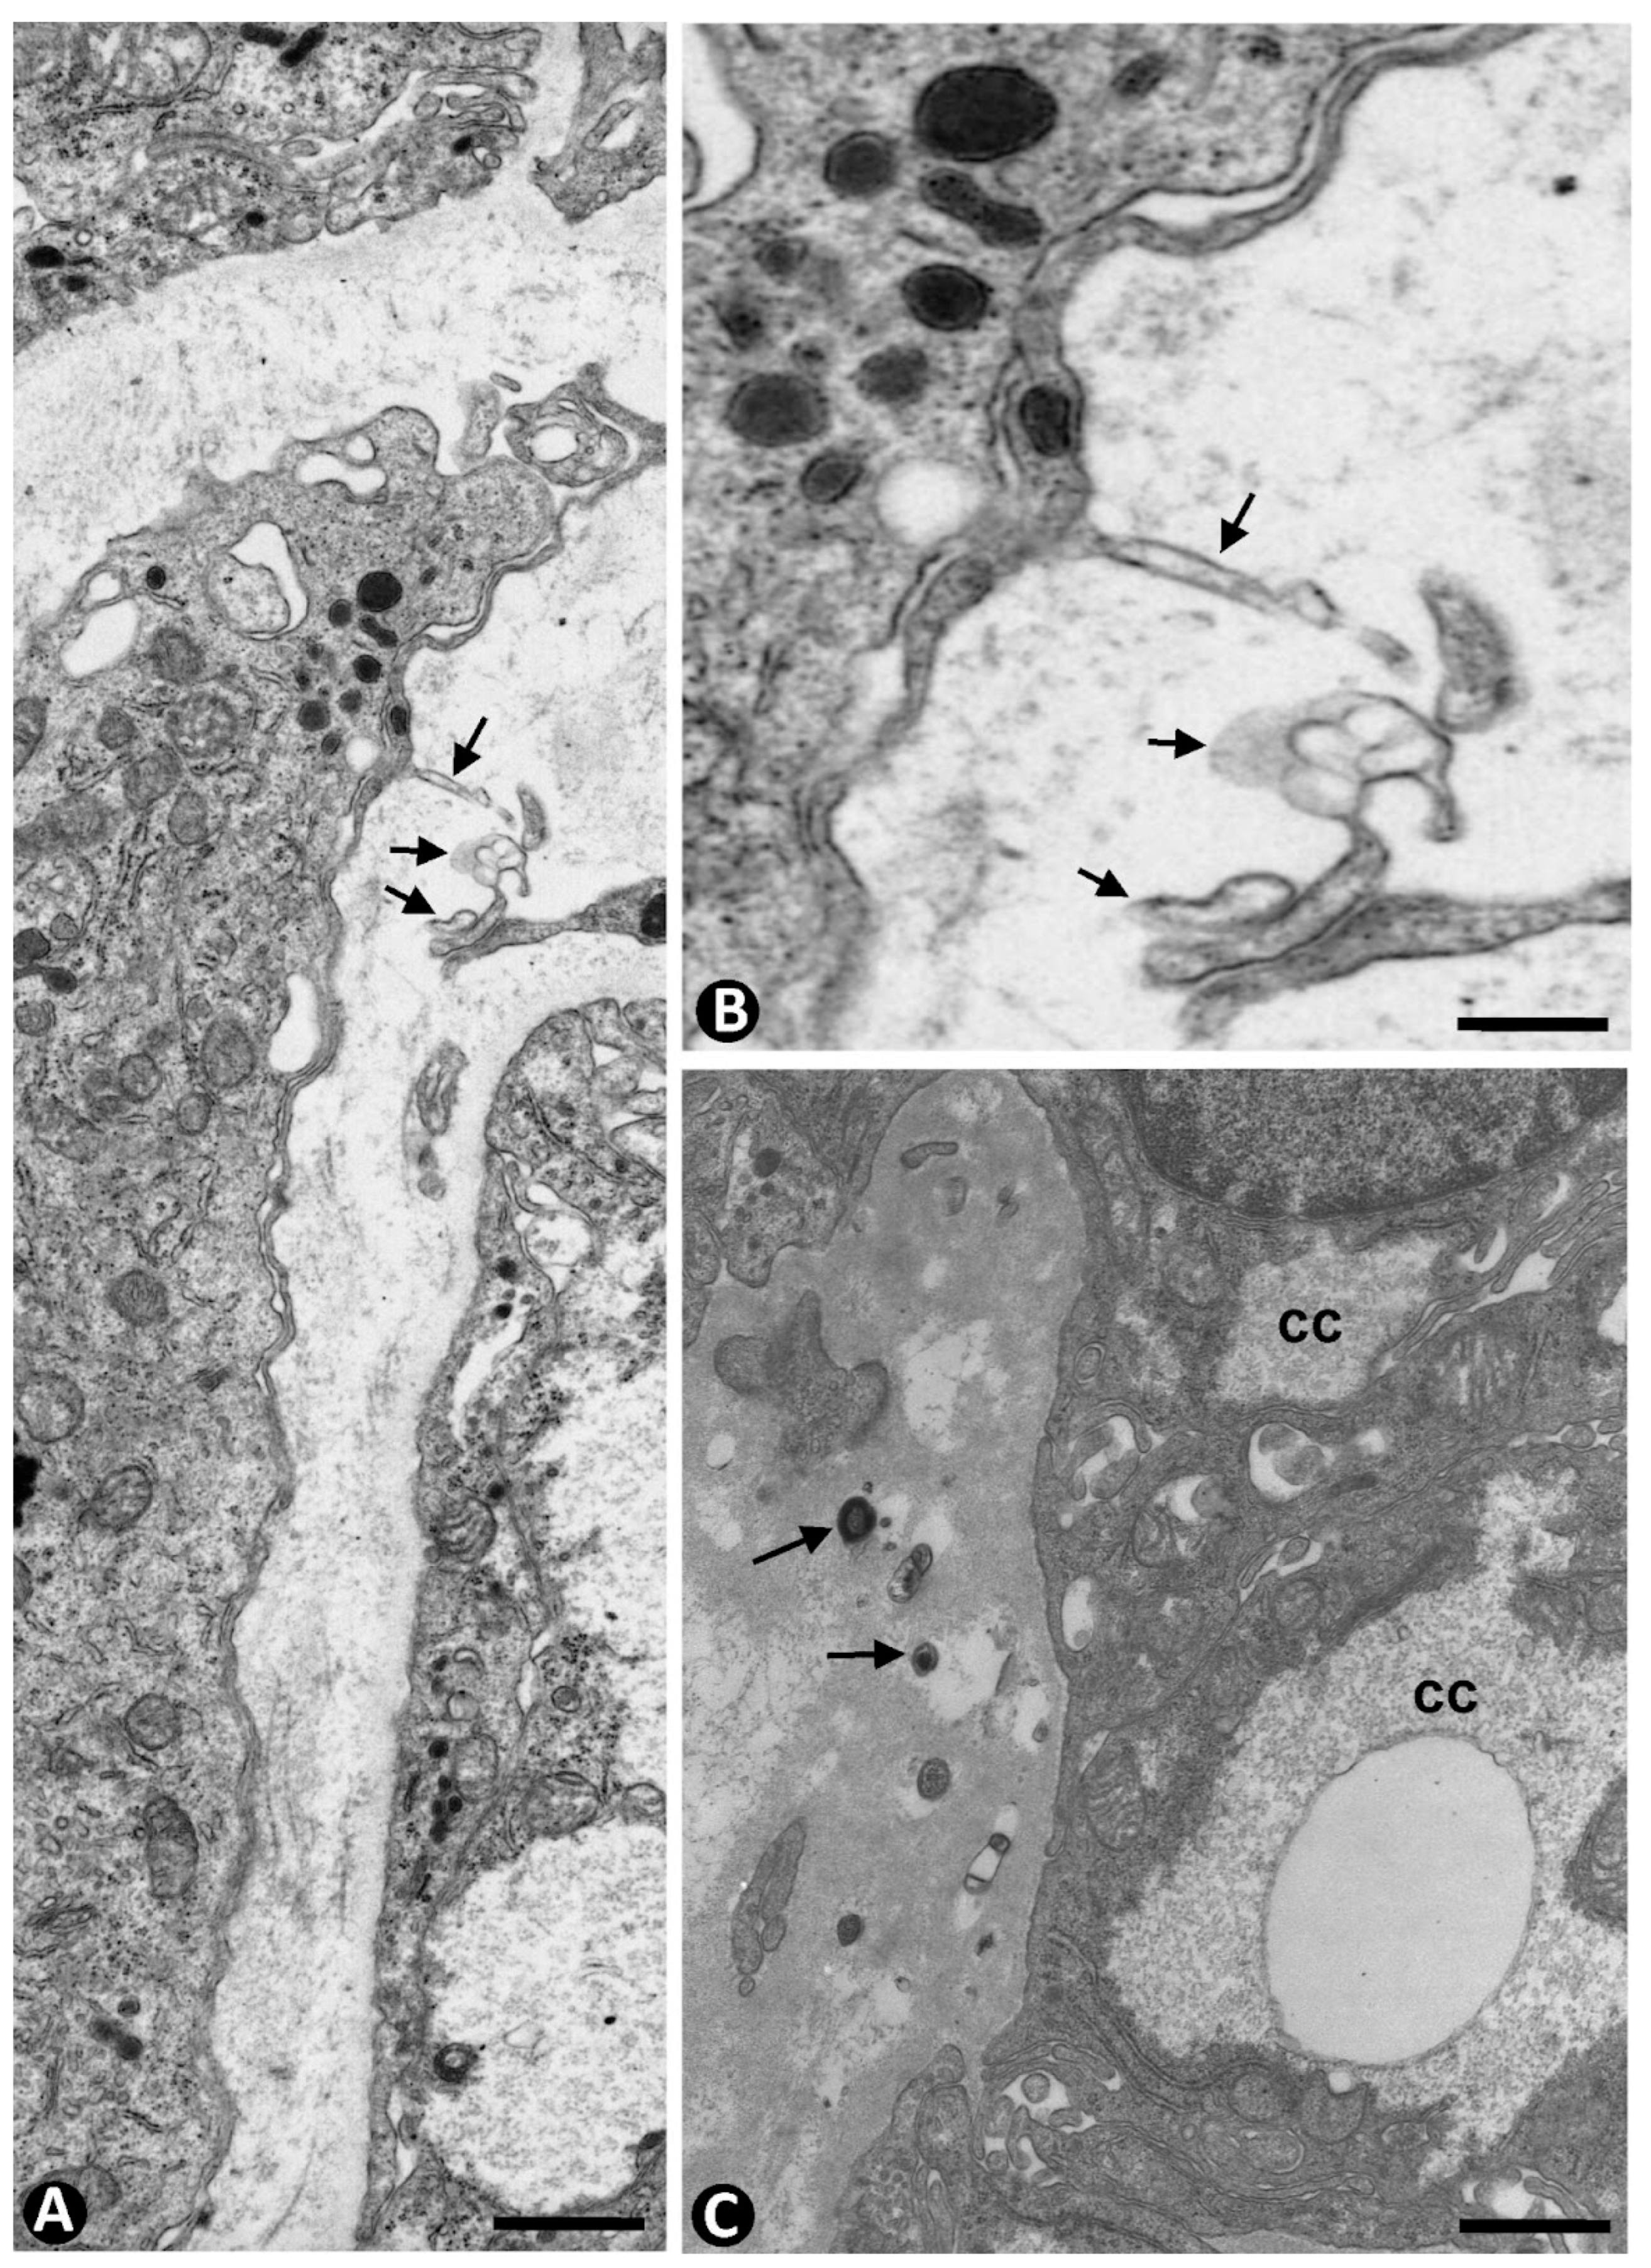

| Common features/similarities of TCs/CD34+ SCs | Small, oval, or triangular somatic body and thin moniliform telopodes Structural components Arrangement in the interstitium, around vessels and surrounding parenchymal nests. Findings of contacting cells, including homo- and hetero-cellular contacts and presence of extracellular vesicles Association with collagen I | ||||